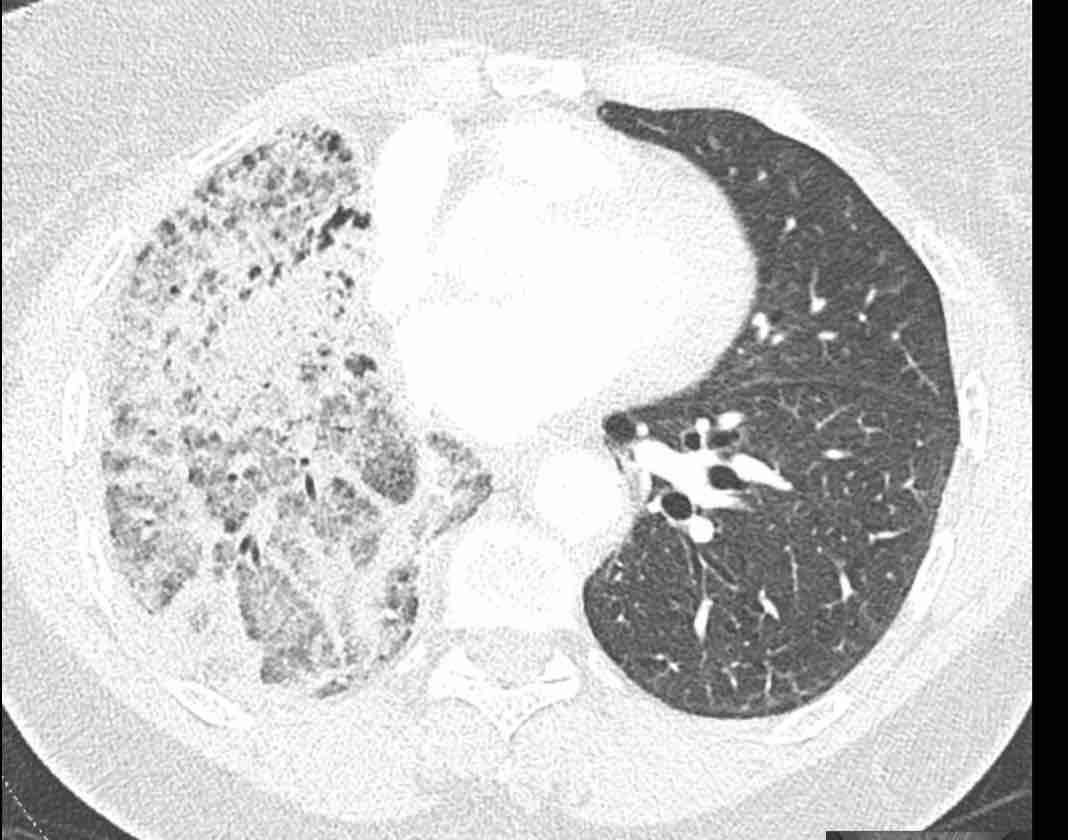

Các hình ảnh này của một bệnh nhân nữ 65 tuổi sau khi đã cắt thùy trên phổi phải trước đó.

Trước tiên, hãy cuộn qua các hình ảnh.

Hình ảnh

Theo dõi lần lượt các phế quản giúp xác định mỏm cắt thùy trên phổi phải (RUL), phế quản thùy giữa bị tắc nghẽn và các phế quản thùy dưới còn thông.

Điều này xác định mô phổi bị di lệch xuống dưới chính là thùy giữa phổi phải (RML), thấy rõ nhất trên mặt phẳng đứng dọc.

Thùy giữa phổi phải bị phù nề và không còn được tưới máu.

Ngoài ra còn thấy hình ảnh ứ máu và xẹp phổi ở các phân thùy đáy của thùy dưới phổi phải (RLL), hiện nằm phía trên thùy giữa phổi phải đã bị nhồi máu.